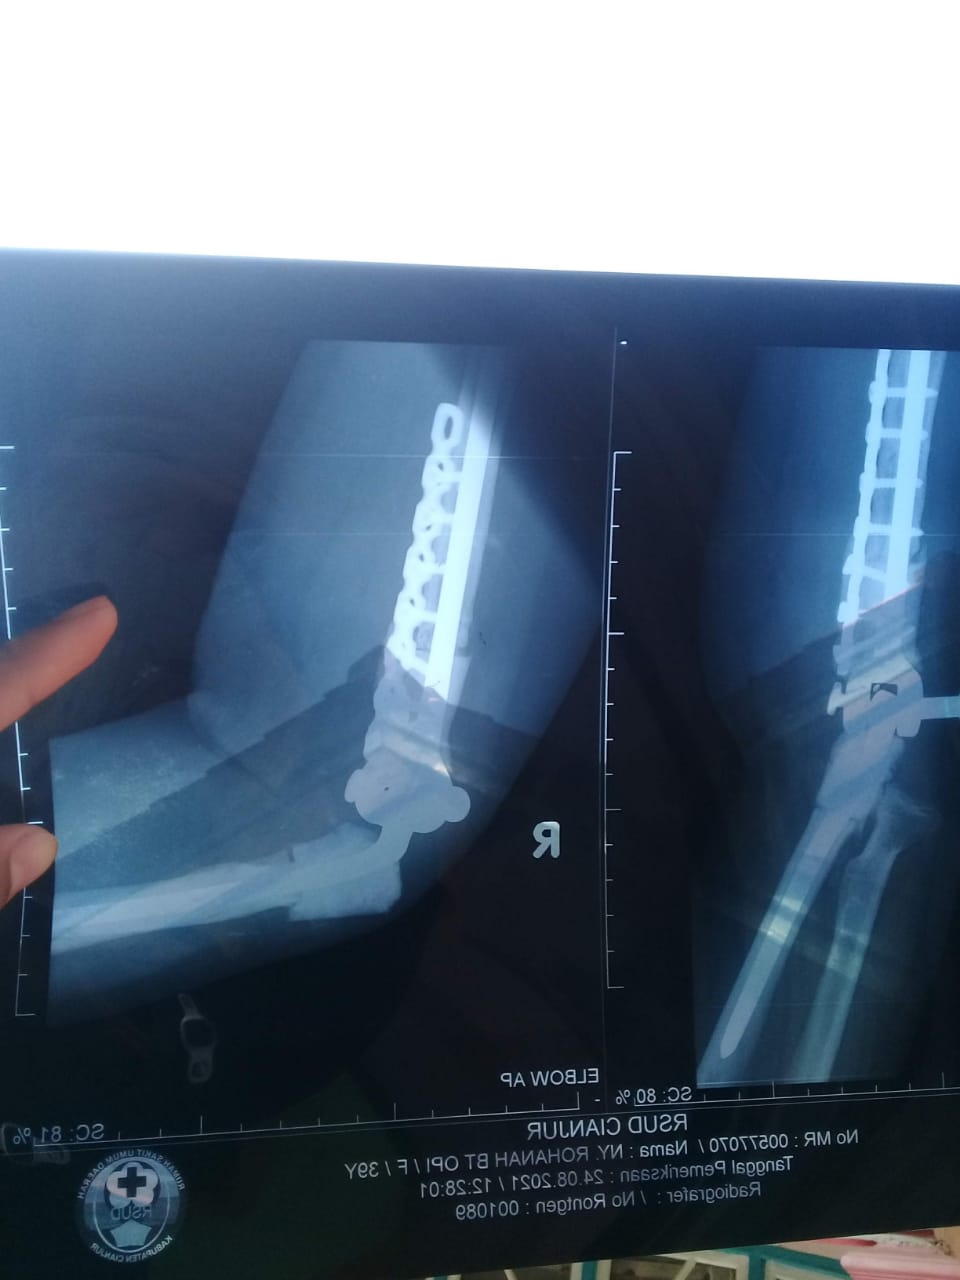

Ibu Rohanah kelahiran cianjur 1981 ini di diagnose Giant cell tumor of the bond a/r antero medial aspect elbow dextra yang mengakibatkan lengan kanannya mengalami benjolan yang semakin membesar

Saat ini bu Rohanah sudah menjalani 3x operasi dan sedang menunggu jadwal operasi ke 4

Tumor yang telah beberapa kali dilakukan pengangkatan tumbuh kembali sehingga mengharuskan bu Rohanah menjalani beberapa kali operasi